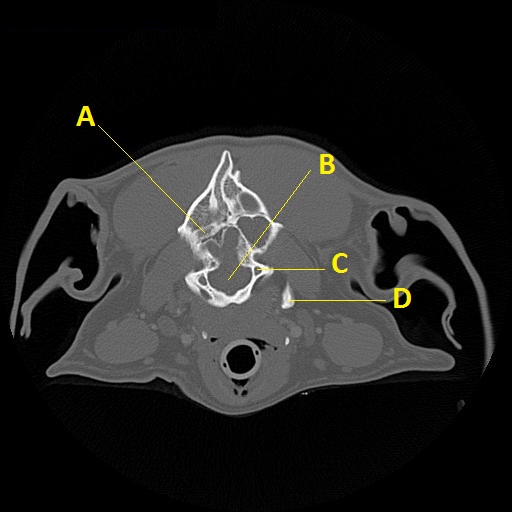

Q. Identify the structures labeled below:

A.

A. canal for the transverse sinus

B. foramen magnum

C. condyloid canal

D. paracondylar process